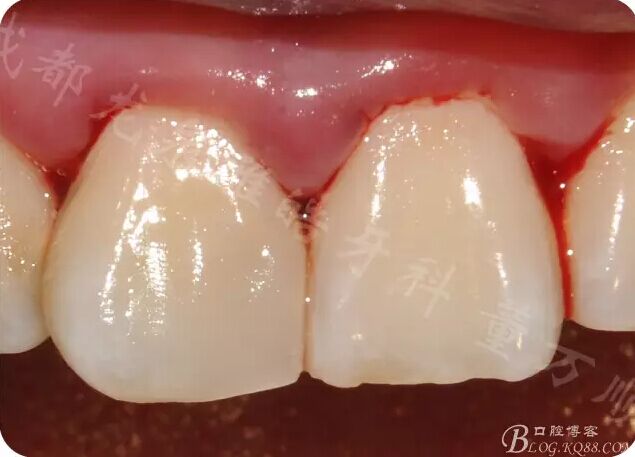

遠中鄰面 預(yù)備過渡到自潔區(qū) 與牙體長軸呈L型(圖片由于相機曝光調(diào)了 不是很自然)